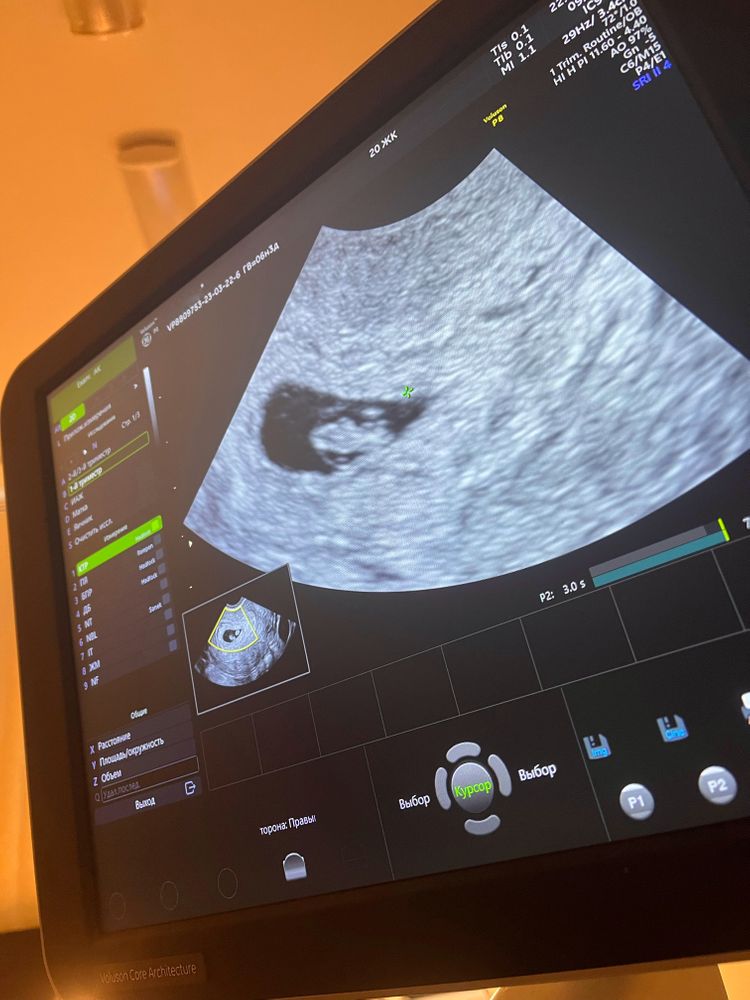

Узи на 6н3д

Ктр нового человека 0.86 см, как сказала врач «ух, большой, почти сантиметр»😂 С дочерью была на узи в 6н5д ктр был 0,69 см☺️ размеры плодного яйца 23мм💪🏽

На узи 12 дней назад ( 4н5д) яйцо было в 3 раза меньше, всего 7мм! А эмбриона так вообще было не видно!